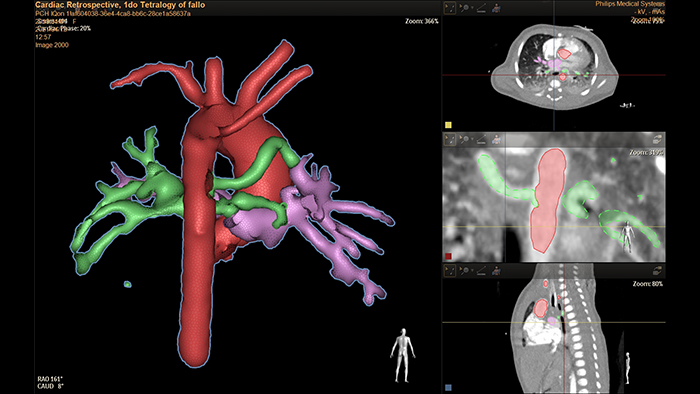

HeartNavigator is a CT planning and live guidance solution using automatic heart model segmentation. It facilitates procedure planning, provides confidence before entering the examination room by having planning information at hand, and adds the ability to overlay planned targets, landing zones, and anatomical boundaries onto live fluoroscopy. In the example above, HeartNavigator is used to segment and visualize aorto-pulmonary collaterals in a 1-day old child with Tetralogy of Fallot. These segmentations can then be used as fluoroscopic overlays to facilitate navigation and reduce contrast injections.